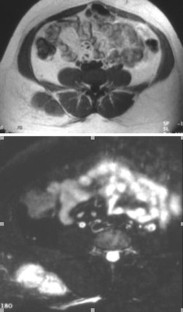

Paraspinal enthesis image This picture representes paraspinal enthesis.